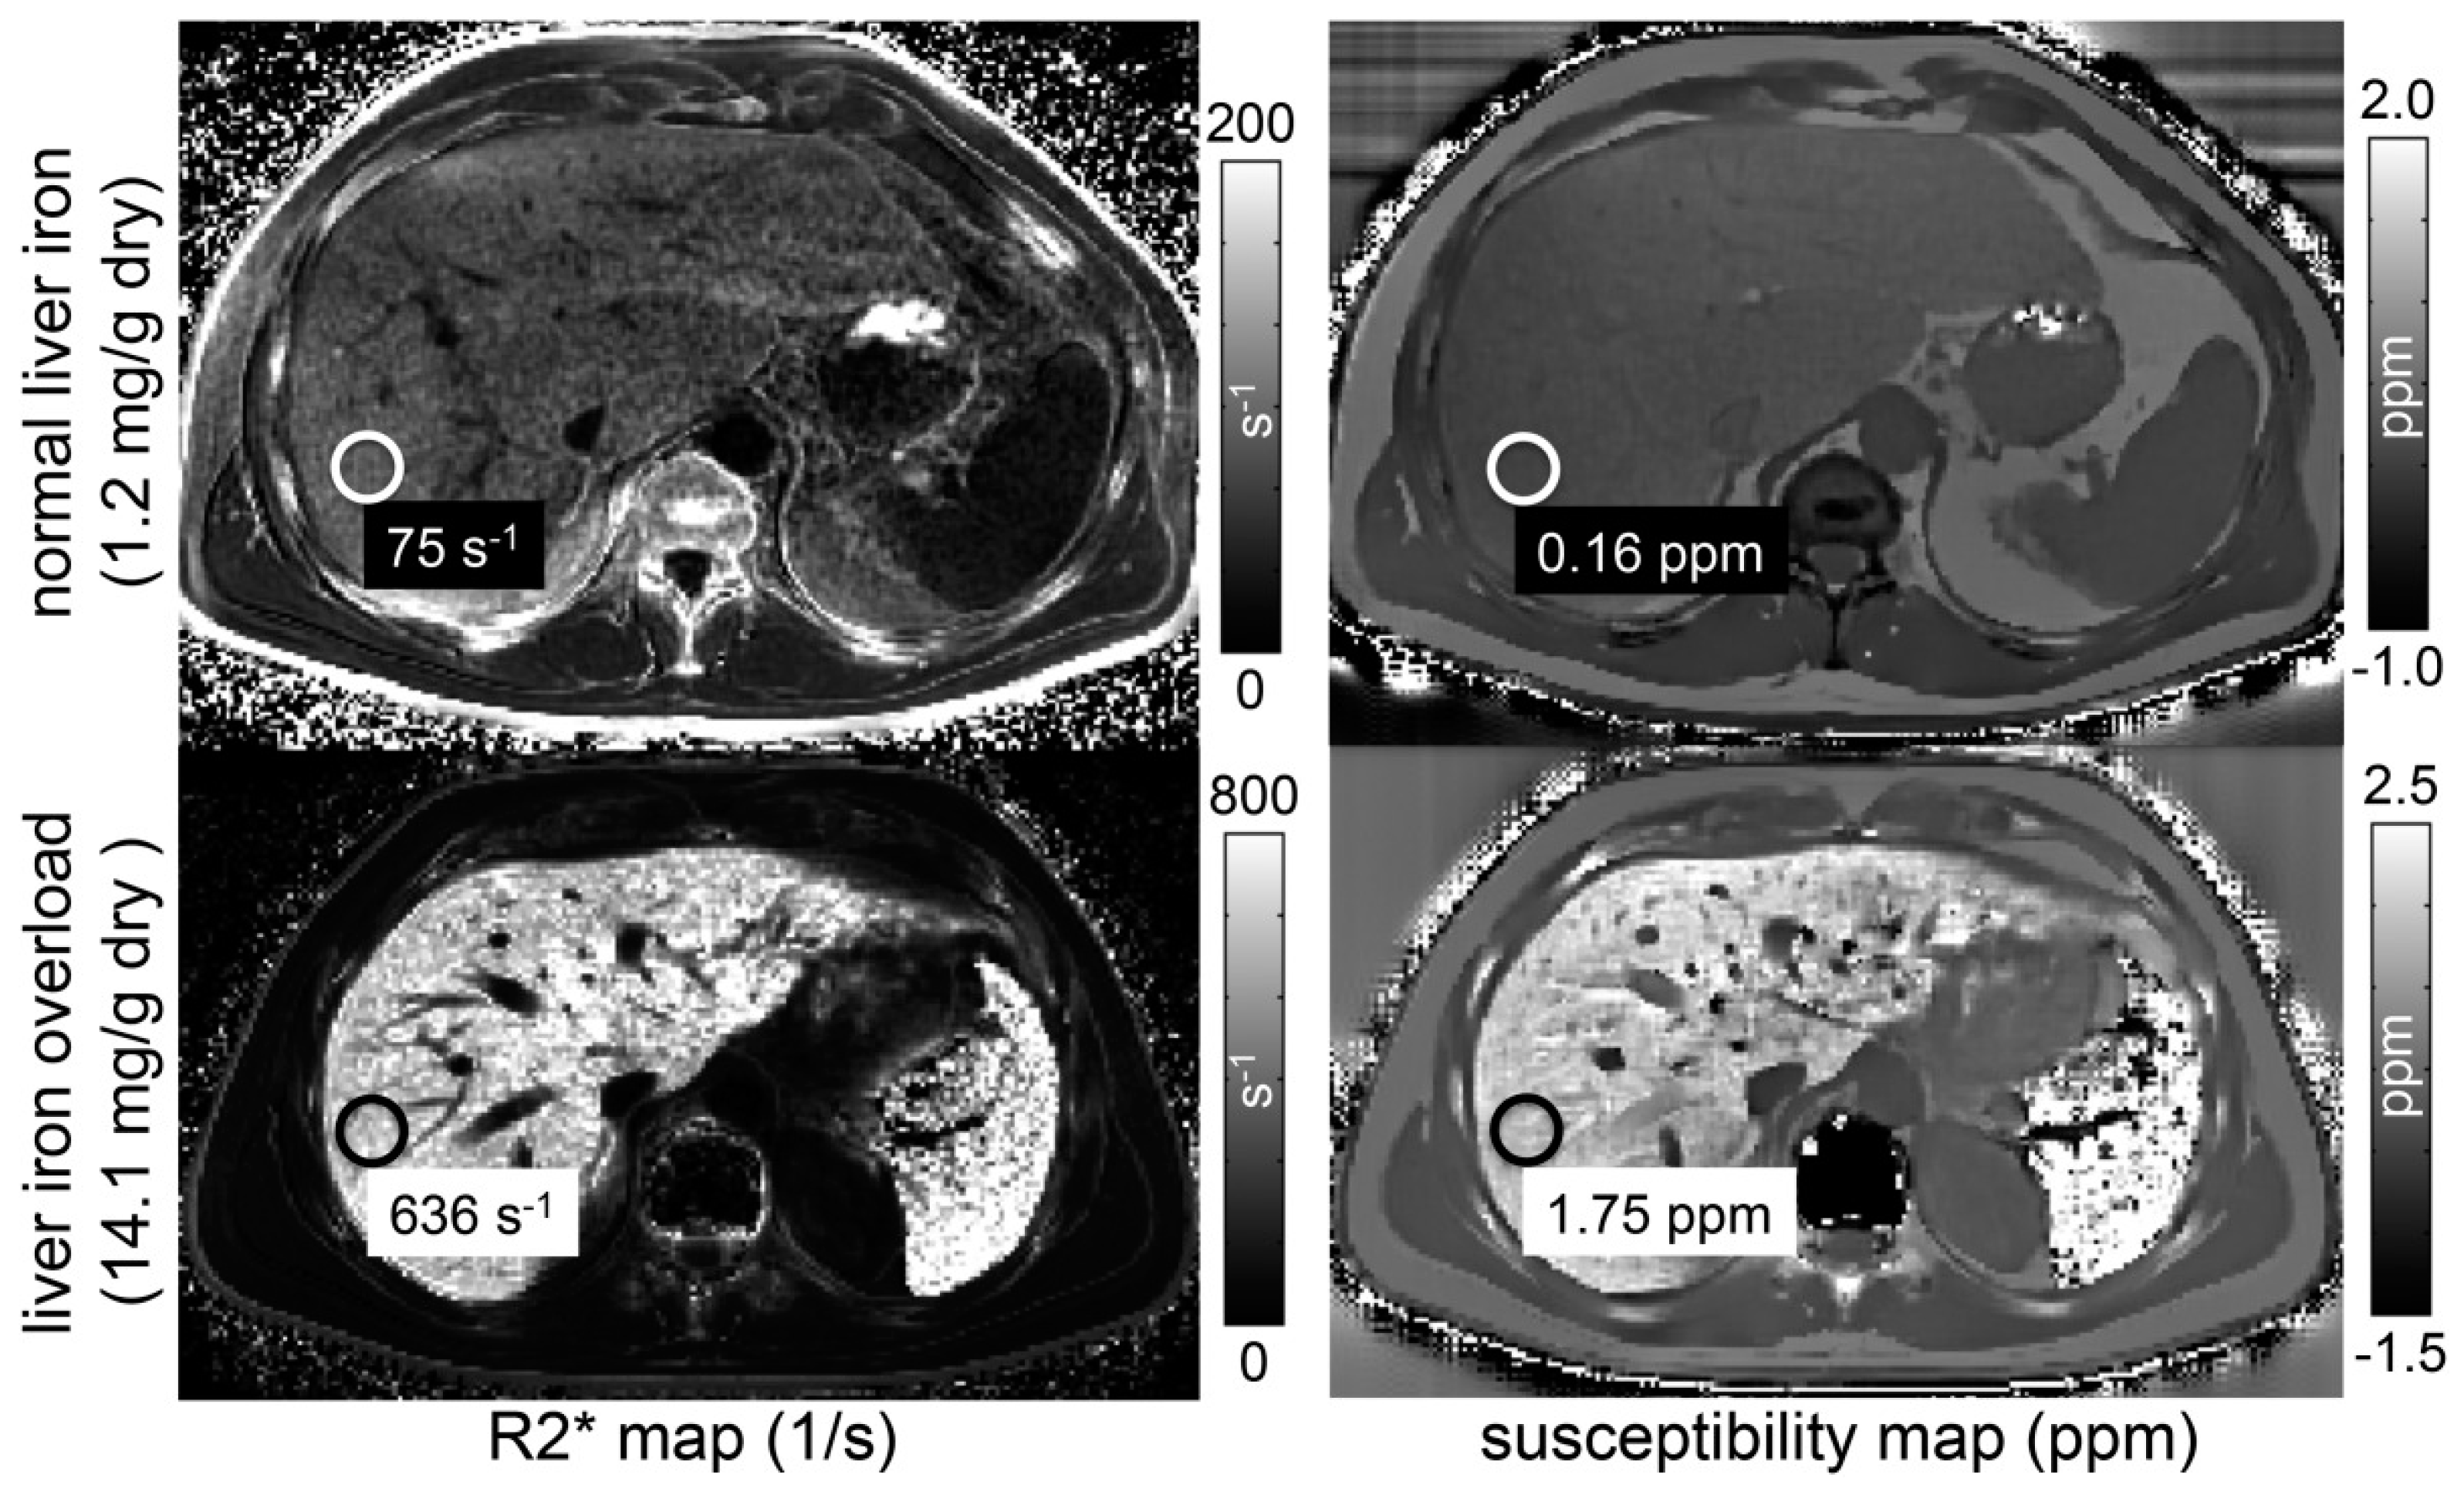

2.2.4. Susceptibility-Weighted Imaging (SWI) and Quantitative Susceptibility Mapping (QSM)